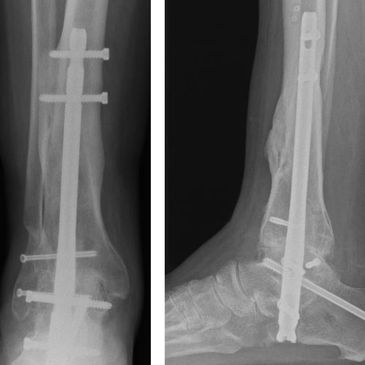

Ankle fusion (arthrodesis) is an effective surgical option for end-stage ankle arthritis that hasn’t improved with conservative care. It provides long-term pain relief and improved stability for everyday walking.

Hindfoot fusion surgery is used to treat severe arthritis, deformity or instability affecting the back of the foot. By permanently stabilising the affected joints, it relieves pain and improves walking comfort.